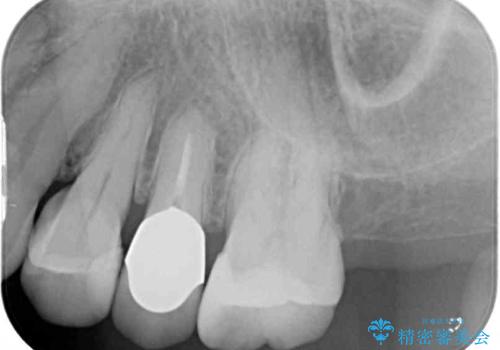

- 歯肉が退縮したためにクラウンの縁や歯根が見えてしまっていることを気にして来院された患者様です。

強い咬合力や磨きすぎなどにより、歯根が見えてしまったり、金属の縁が見えてしまったりし、審美障害を引き起こすことがあります。

歯根が変色してしまうと、歯肉越しに歯根の黒い色が透けてしまうことがあり、この点についてはどうにも施しようがないため、患者様には事前のご理解いただきました。